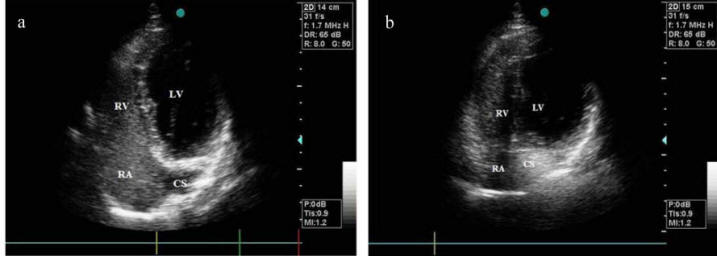

2 and 3 dimension transesophageal echocardiography images of the coronary sinus and middle cardiac vein in a patient with severe calcific aortic stenosis. The coronary venous system is an elaborate array of vascular tributaries that ultimately drain into the coronary sinus (figure 2). This is an apical 4 chamber with the arrow on the posterior mitral leaflet. Apical 4 chamber coronary sinus echocardiography images for diagnosing normal echocardiogram congenital heart defects. Parasternal long axis right ventricular outflow landmarks (tilt toward left shoulder ).

Learn vocabulary, terms and more with flashcards, games and other study tools. The normal heart functions almost exclusively as an aerobic organ with little capacity for anaerobic metabolism to produce energy. Rupture of sinus of valsalva aneurysm of left coronary sinus. 2 and 3 dimension transesophageal echocardiography images of the coronary sinus and middle cardiac vein in a patient with severe calcific aortic stenosis. The coronary sinus is the largest cardiac venous structure. The probe is placed below the sternum with an overhand grip pointing toward the left shoulder. Echo report cad thinned & akinetic rca & lad territories, severe lv/rv systolic dysfunction,dilated ra, rv & la, moderate mr, mild tr, large multiple clots in rv& lv apex, no pe , bilateral pleural effusion+ case 52 : It is present in all mammals, including humans. This position encompasses several different views of the lv in short axis that differ in how basal or apical the probe is. Sinus node dysfunction (sick sinus syndrome) sss. Cut plane of the coronary sinus view. Apical 4 chamber coronary sinus echocardiography images for diagnosing normal echocardiogram congenital heart defects. Total anomalous pulmonary venous return to the coronary sinus.